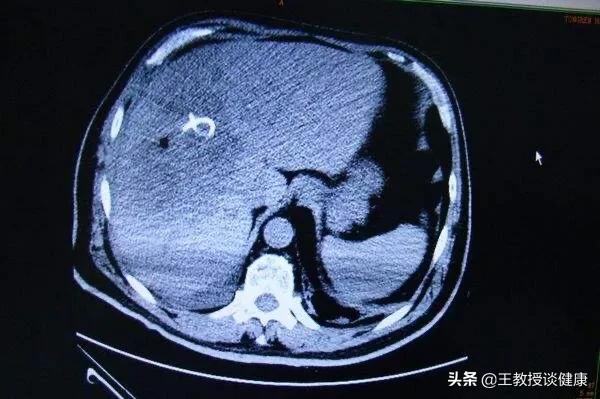

CT所见肝右叶肝脓肿明显液化影像

全身应用有效抗生素一周的影像